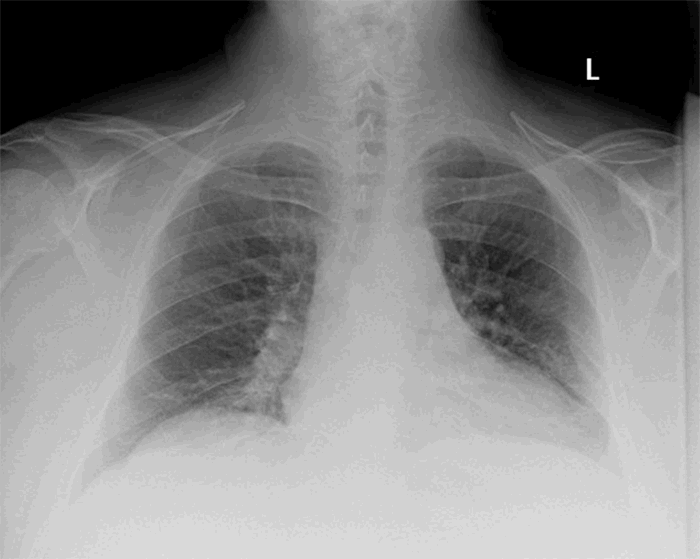

Upon presentation, the patient’s temperature was 36.8°C, pulse 109 bpm, blood pressure 133/110 mmHg, and oxygen saturation 94 percent on room air. He was noted to be significantly dyspneic and diaphoretic with decreased breath sounds on the left on examination. The patient’s presentation, combined with a review of the CT scan, raised the concern for tension physiology. Therefore, the patient was taken emergently to the operating room for a left video-assisted thoracoscopy and evacuation of the hematoma. A tube thoracostomy was not placed in the trauma bay due to concern for further dissection of the parietal pleura from the chest wall and anticipated poor drainage of the already clotted hematoma. In the operating room, a dual-lumen endotracheal tube was placed upon induction. A 10 mm incision was made in the posterior axillary line at the fifth intercostals space, and the hematoma cavity was entered where extensive organized clot and some fresh blood was encountered and removed with suctioning. A second incision was then made at the same level in the anterior axillary line, and the pleural cavity was then accessed with the thoracoscope. This procedure allowed direct visualization of the remaining hematoma, which extended posteriorly. There was minimal serosanguinous fluid in the pleural space, confirming that the hematoma was extrapleural. The pleura was incised, and the remainder of the hematoma was drained through the pleural space. The hematoma cavity was examined, and no further signs of active bleeding were noted. There was no injury to the lung parenchyma. Two 32 French tube thoracostomies were placed in posterior basal and anterior apical positions. The patient remained intubated, was transferred to the surgical intensive care unit for further management and successfully extubated on postoperative day one. The anterior chest tube was removed on postoperative day two, and the posterior tube was removed on postoperative day three. He was then discharged home in good condition on postoperative day four. The patient was seen in the clinic for follow-up at one month with no intra-thoracic abnormalities noted on the chest radiograph (Figure 3) and full resolution of symptoms.

Figure 3. Chest radiograph at one month postdischarge during follow up clinic appointment